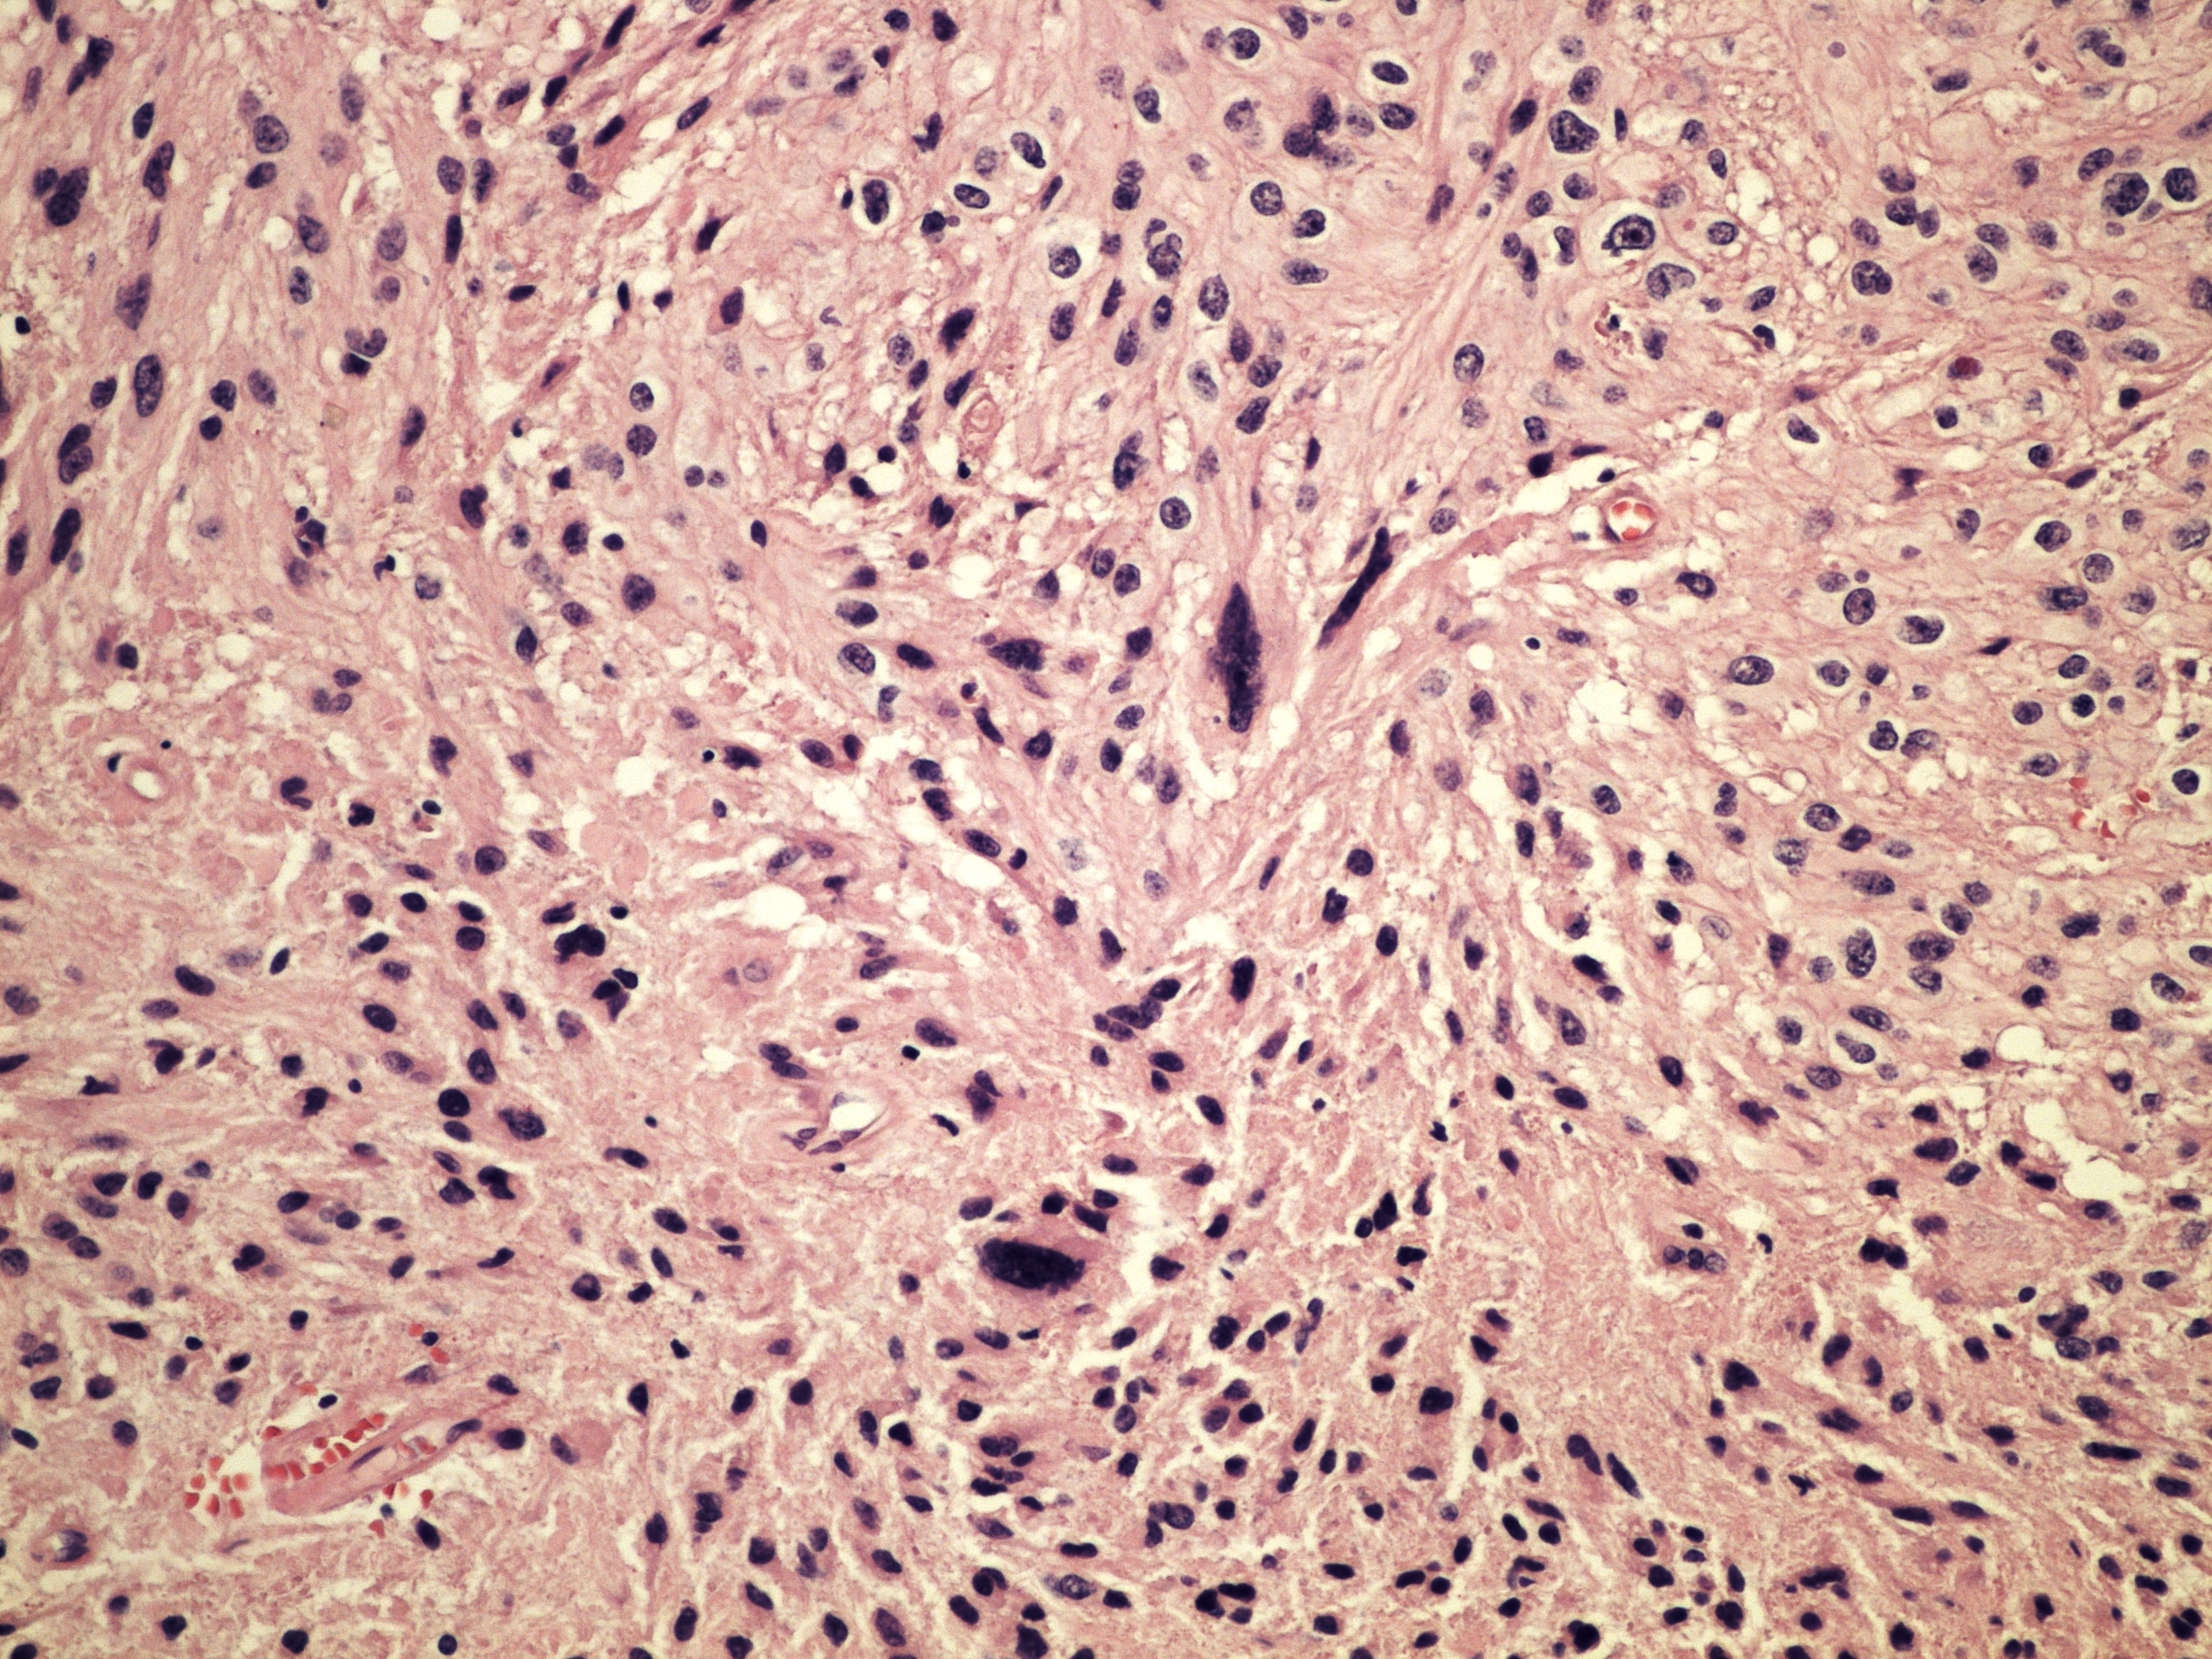

Микрофотографии гистологии глиобластомы головного мозга